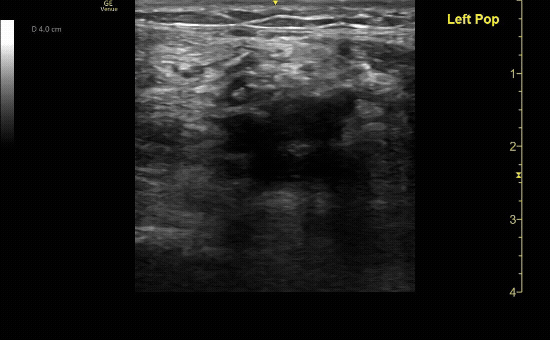

Positive DVT ultrasound showing the bifurcation of the popliteal vein with incomplete compression of the popliteal vein.

c/o Matthew Hughes, MD